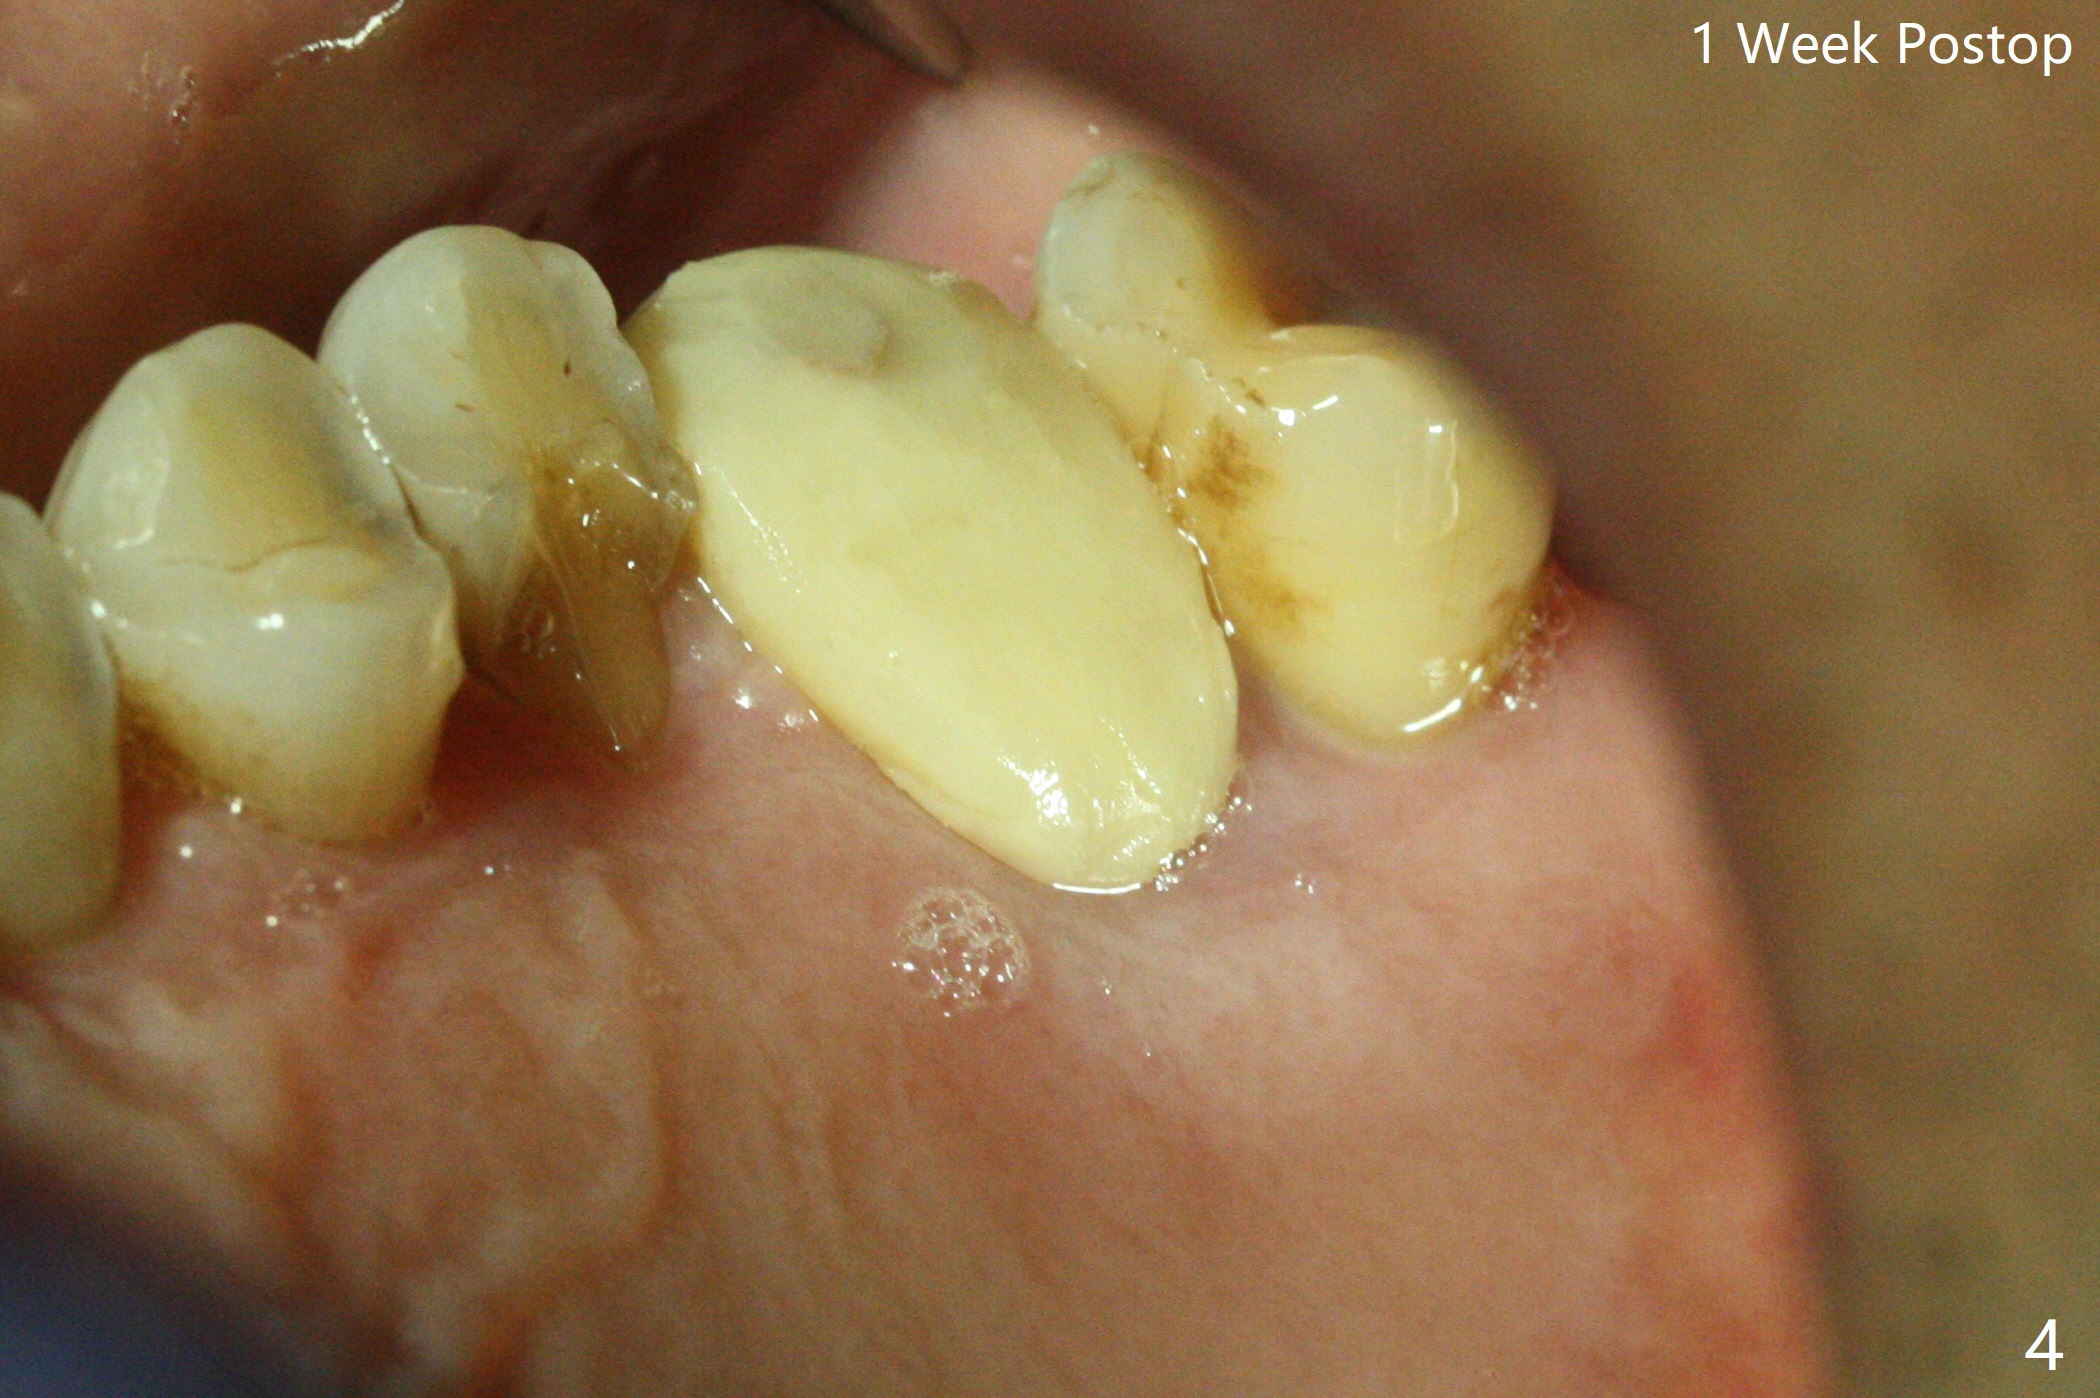

尽管14号牙远中裂纹(图一:箭头),冷热痛,拔除时腭侧根表面覆盖结石,似乎没有牙周膜附着。虽然牙龈萎缩不明显(图二:箭头),拔除后检查显示腭侧骨板缺失一直到根尖。使用10.5 和12毫米bone trimmers后中隔平面偏向近中,使用设计最后一个钻头(3x10mm)后,钻洞已经进入近中颊侧牙槽窝,由于植入4x9毫米植体扭力高于35 Ncm,使用3.5x7.3,3.5x8.5毫米钻头(也可以减少植体腭侧偏移)后,扭力20Ncm(图三),腭侧一个螺纹暴露。放置基台后,填入粘性骨粉(*),远中颊侧牙槽窝可能与腭侧牙槽窝重叠。制作临时牙冠,衬里,取出牙冠,覆盖PRF后,盖上牙冠,检查牙冠与对合牙分开~1毫米。术后一周临时牙冠与腭侧牙龈接触紧密,覆盖巨大腭侧缺损。如果没有临时牙冠,关闭腭侧缺损谅必困难,可能出现骨粉暴露。